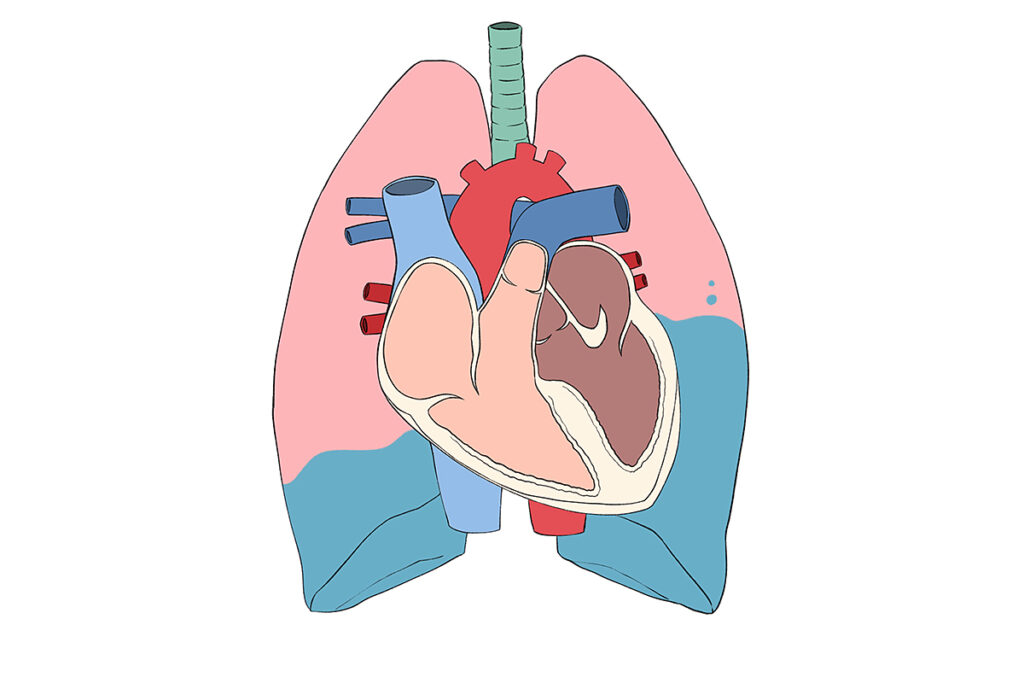

さらに悪化すると、肺⽔腫(肺に⽔が溜まる状態)を起こし、陸にいながら溺れているよ

うな⾮常に苦しい状態になることもあります。